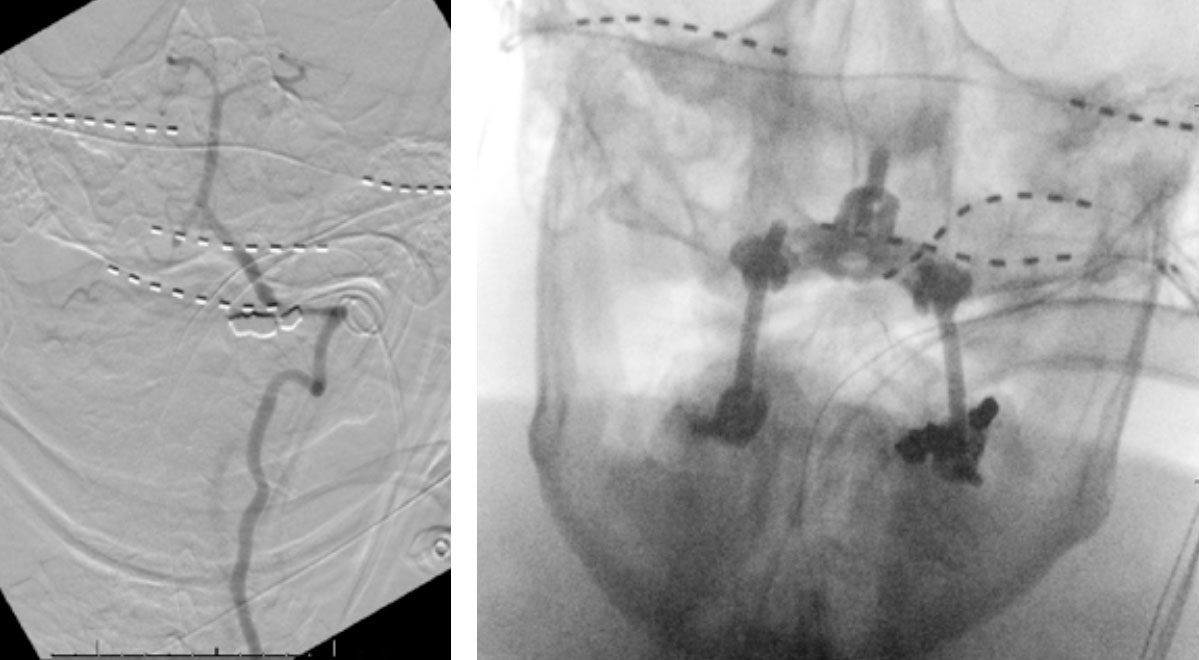

CTA of the neck and brain reveal that the left Vertebral Artery is completely occluded at approximately the C1-C2 level with extensive hypertrophic degenerative osseous changes from C1-C3. Retrograde flow into the post PICA left Vertebral Artery is observed from the co-dominant right Vertebral Artery which appears to be the primary supply into the basilar circulation. No significant Posterior Communicating arteries are observed on either the right or left Carotid Artery on the CTA imaging (Figure 1).

We performed conventional catheter angiography with provocative testing to reproduce his symptoms. The right Vertebral Artery is the codominant primary supply to the basilar circulation with reflux into the distal left Vertebral Artery that is occluded (Figure 3).

During neutral positioning, the vertebrobasilar circulation fills briskly from the Right Vertebral Artery. (Figure 4)